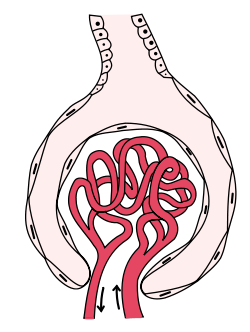

Glomerulus (kidney)

The glomerulus (red) within Bowman's capsule | |

A glomerulus (RP English pronunciation: /ɡlɒˈmɛr(j)uːləs/, American /ɡlɒˈmɛrələs/) is a network (as a tuft) of capillaries located at the beginning of a nephron in the kidney. It serves as the first stage in the filtering process of the blood carried out by the nephron in its formation of urine.

The glomerulus is surrounded by a cup-like sac known as Bowman's capsule. The blood plasma is filtered through the capillaries of the glomerulus into the capsule. The Bowman's capsule empties the filtrate into the proximal tubule that is also part of the duct system of the nephron.

A glomerulus receives its blood supply from an afferent arteriole of the renal circulation. Unlike most other capillary beds, the glomerulus drains into an efferent arteriole rather than a venule. The resistance of these arterioles results in high pressure within the glomerulus, aiding the process of ultrafiltration, where fluids and soluble materials in the blood are forced out of the capillaries and into Bowman's capsule.

A glomerulus and its surrounding Bowman's capsule constitute a renal corpuscle, the basic filtration unit of the kidney.[1] The rate at which blood is filtered through all of the glomeruli, and thus the measure of the overall renal function, is the glomerular filtration rate (GFR).